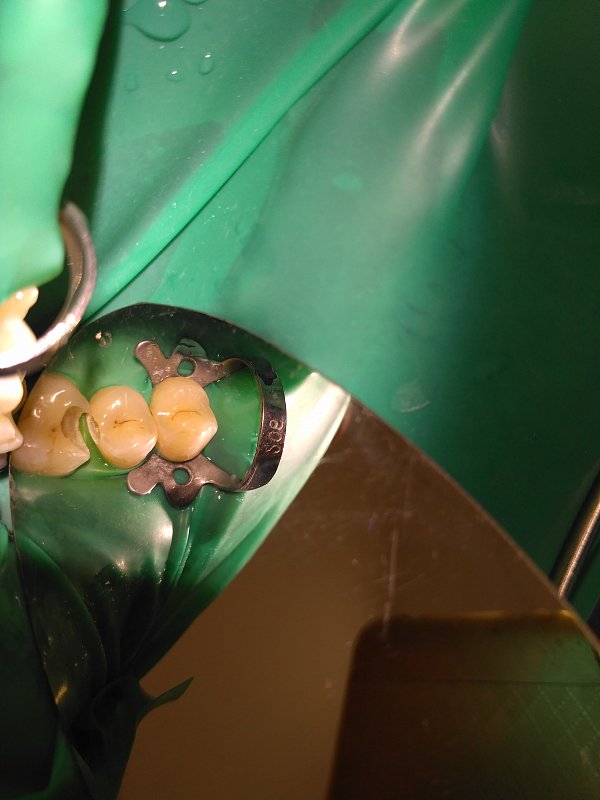

Пациент обратился с жалобами на кариес зубов.

Исходное состояние: Зубы под реставрациями неудовлетворяющими клиническим требованиям

Выполнена реставрация накладками из прессованной керамики.